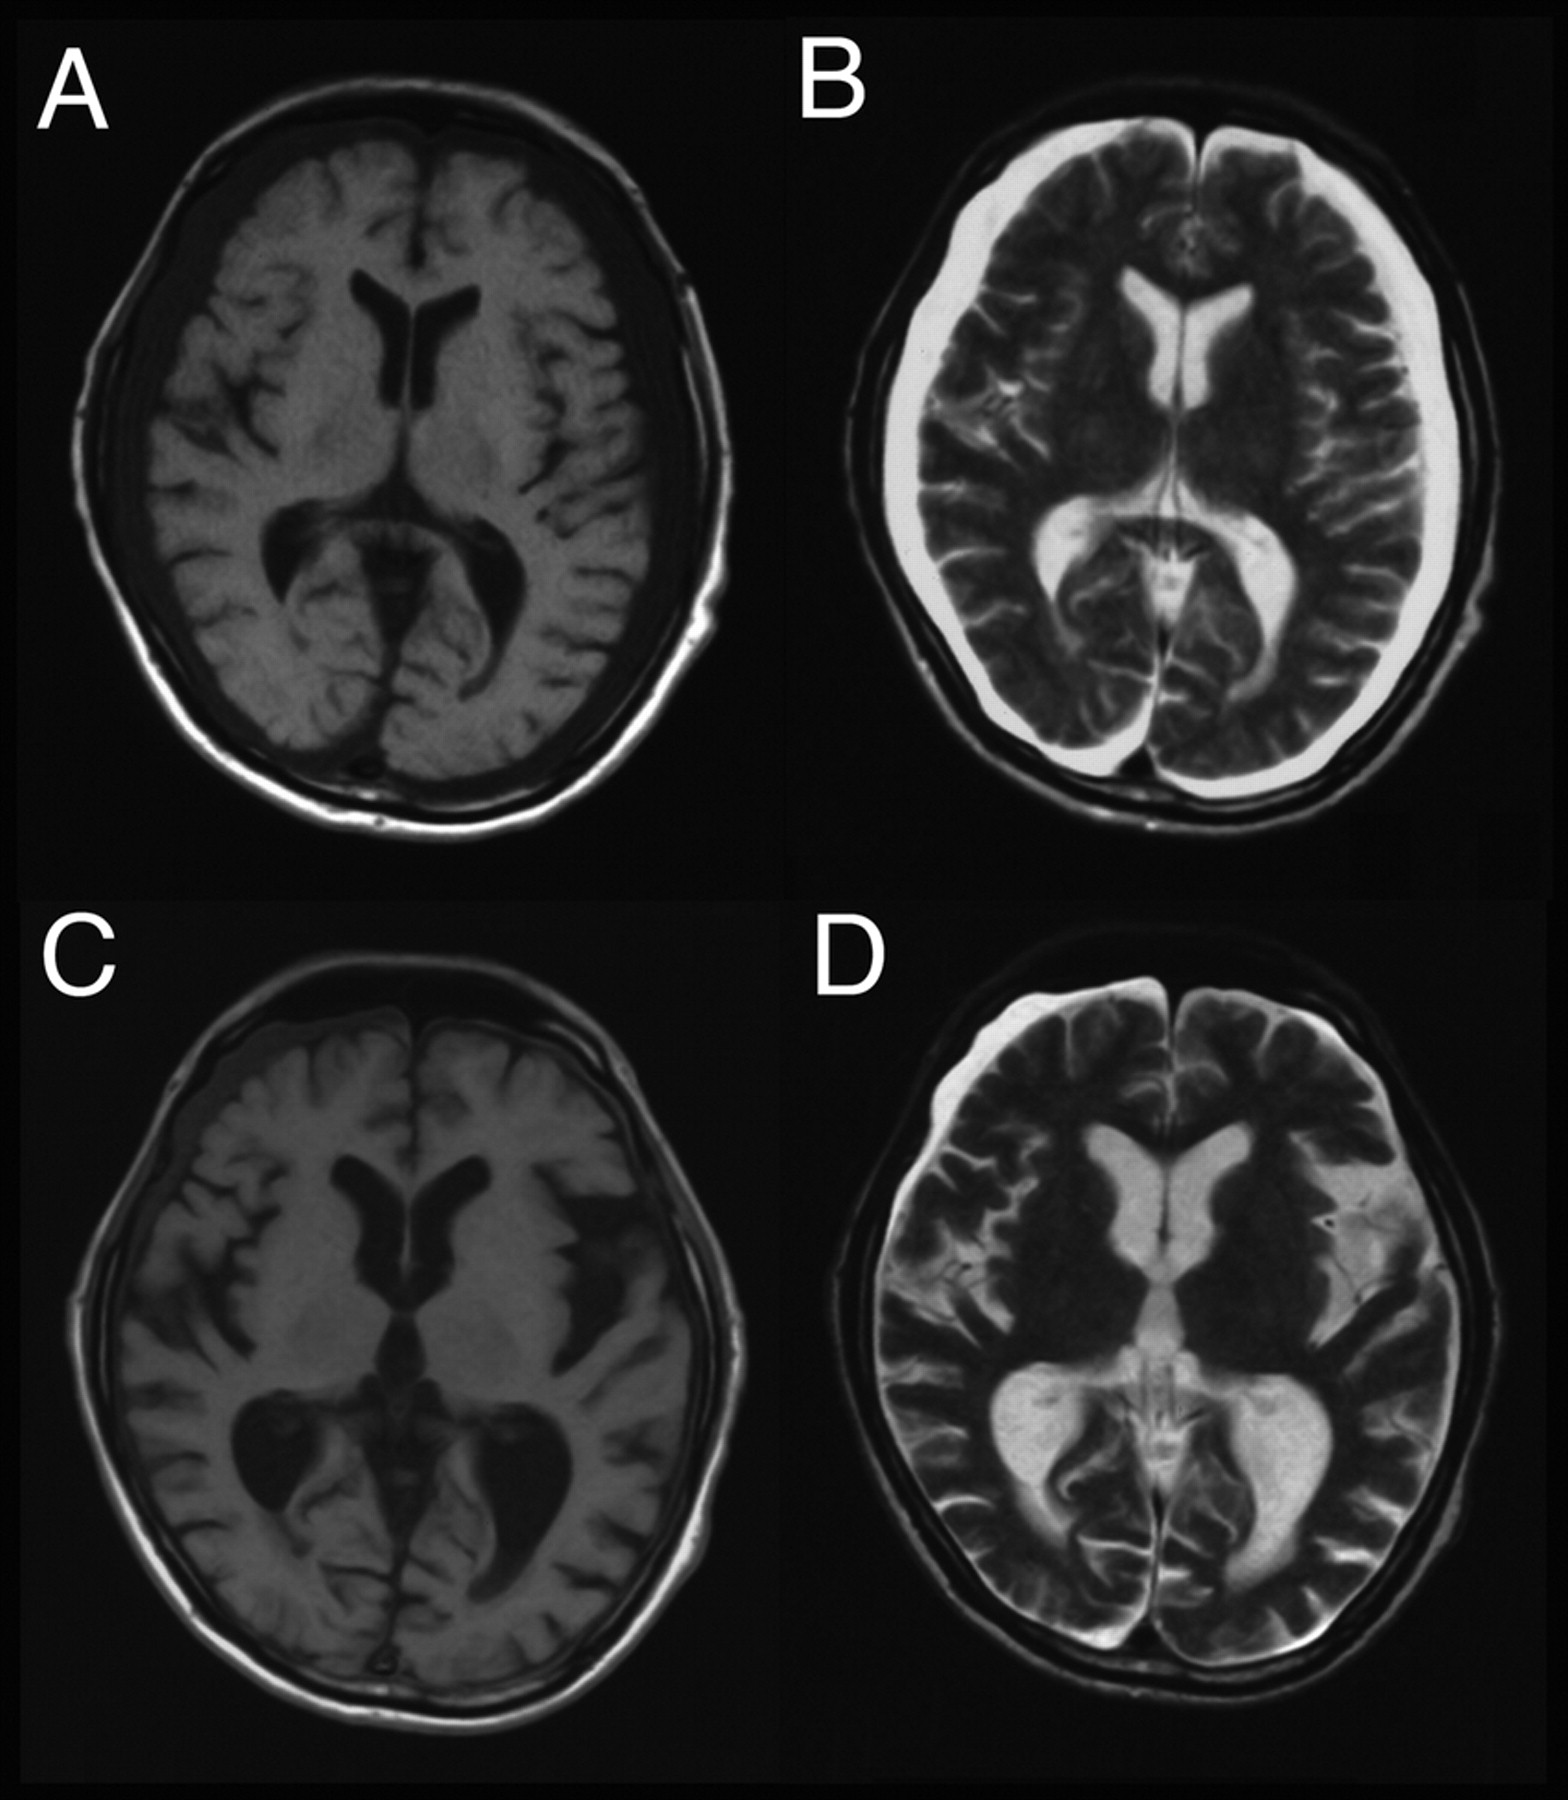

一个73岁的老人出现呕吐、颤抖,意识障碍12小时后食用酱油,试图自杀。他的血钠188毫克当量/ L和氯142毫克当量/ L。血清渗透性高314 mOsm /公斤H2o . T1和t2加权脑部MRI显示对称大脑萎缩和硬膜下液体收集在大脑皮层(图中,A和B)。在诊断急性血钠过多由于摄取过多氯化钠,我们纠正他的血钠过多在未来48小时内,和他的条件迅速改善。没有观察到肾脏功能障碍。评价脑容量恢复,我们重复MRI 3周后出现。尽管一些硬膜下液体收集器似乎依然存在,脑容量恢复(图中,C和D)。急性血钠过多收缩大脑通过脱水。1我们的案例表明,可逆的大脑萎缩和补偿扩大硬膜下腔是大脑脱水的金字招牌。